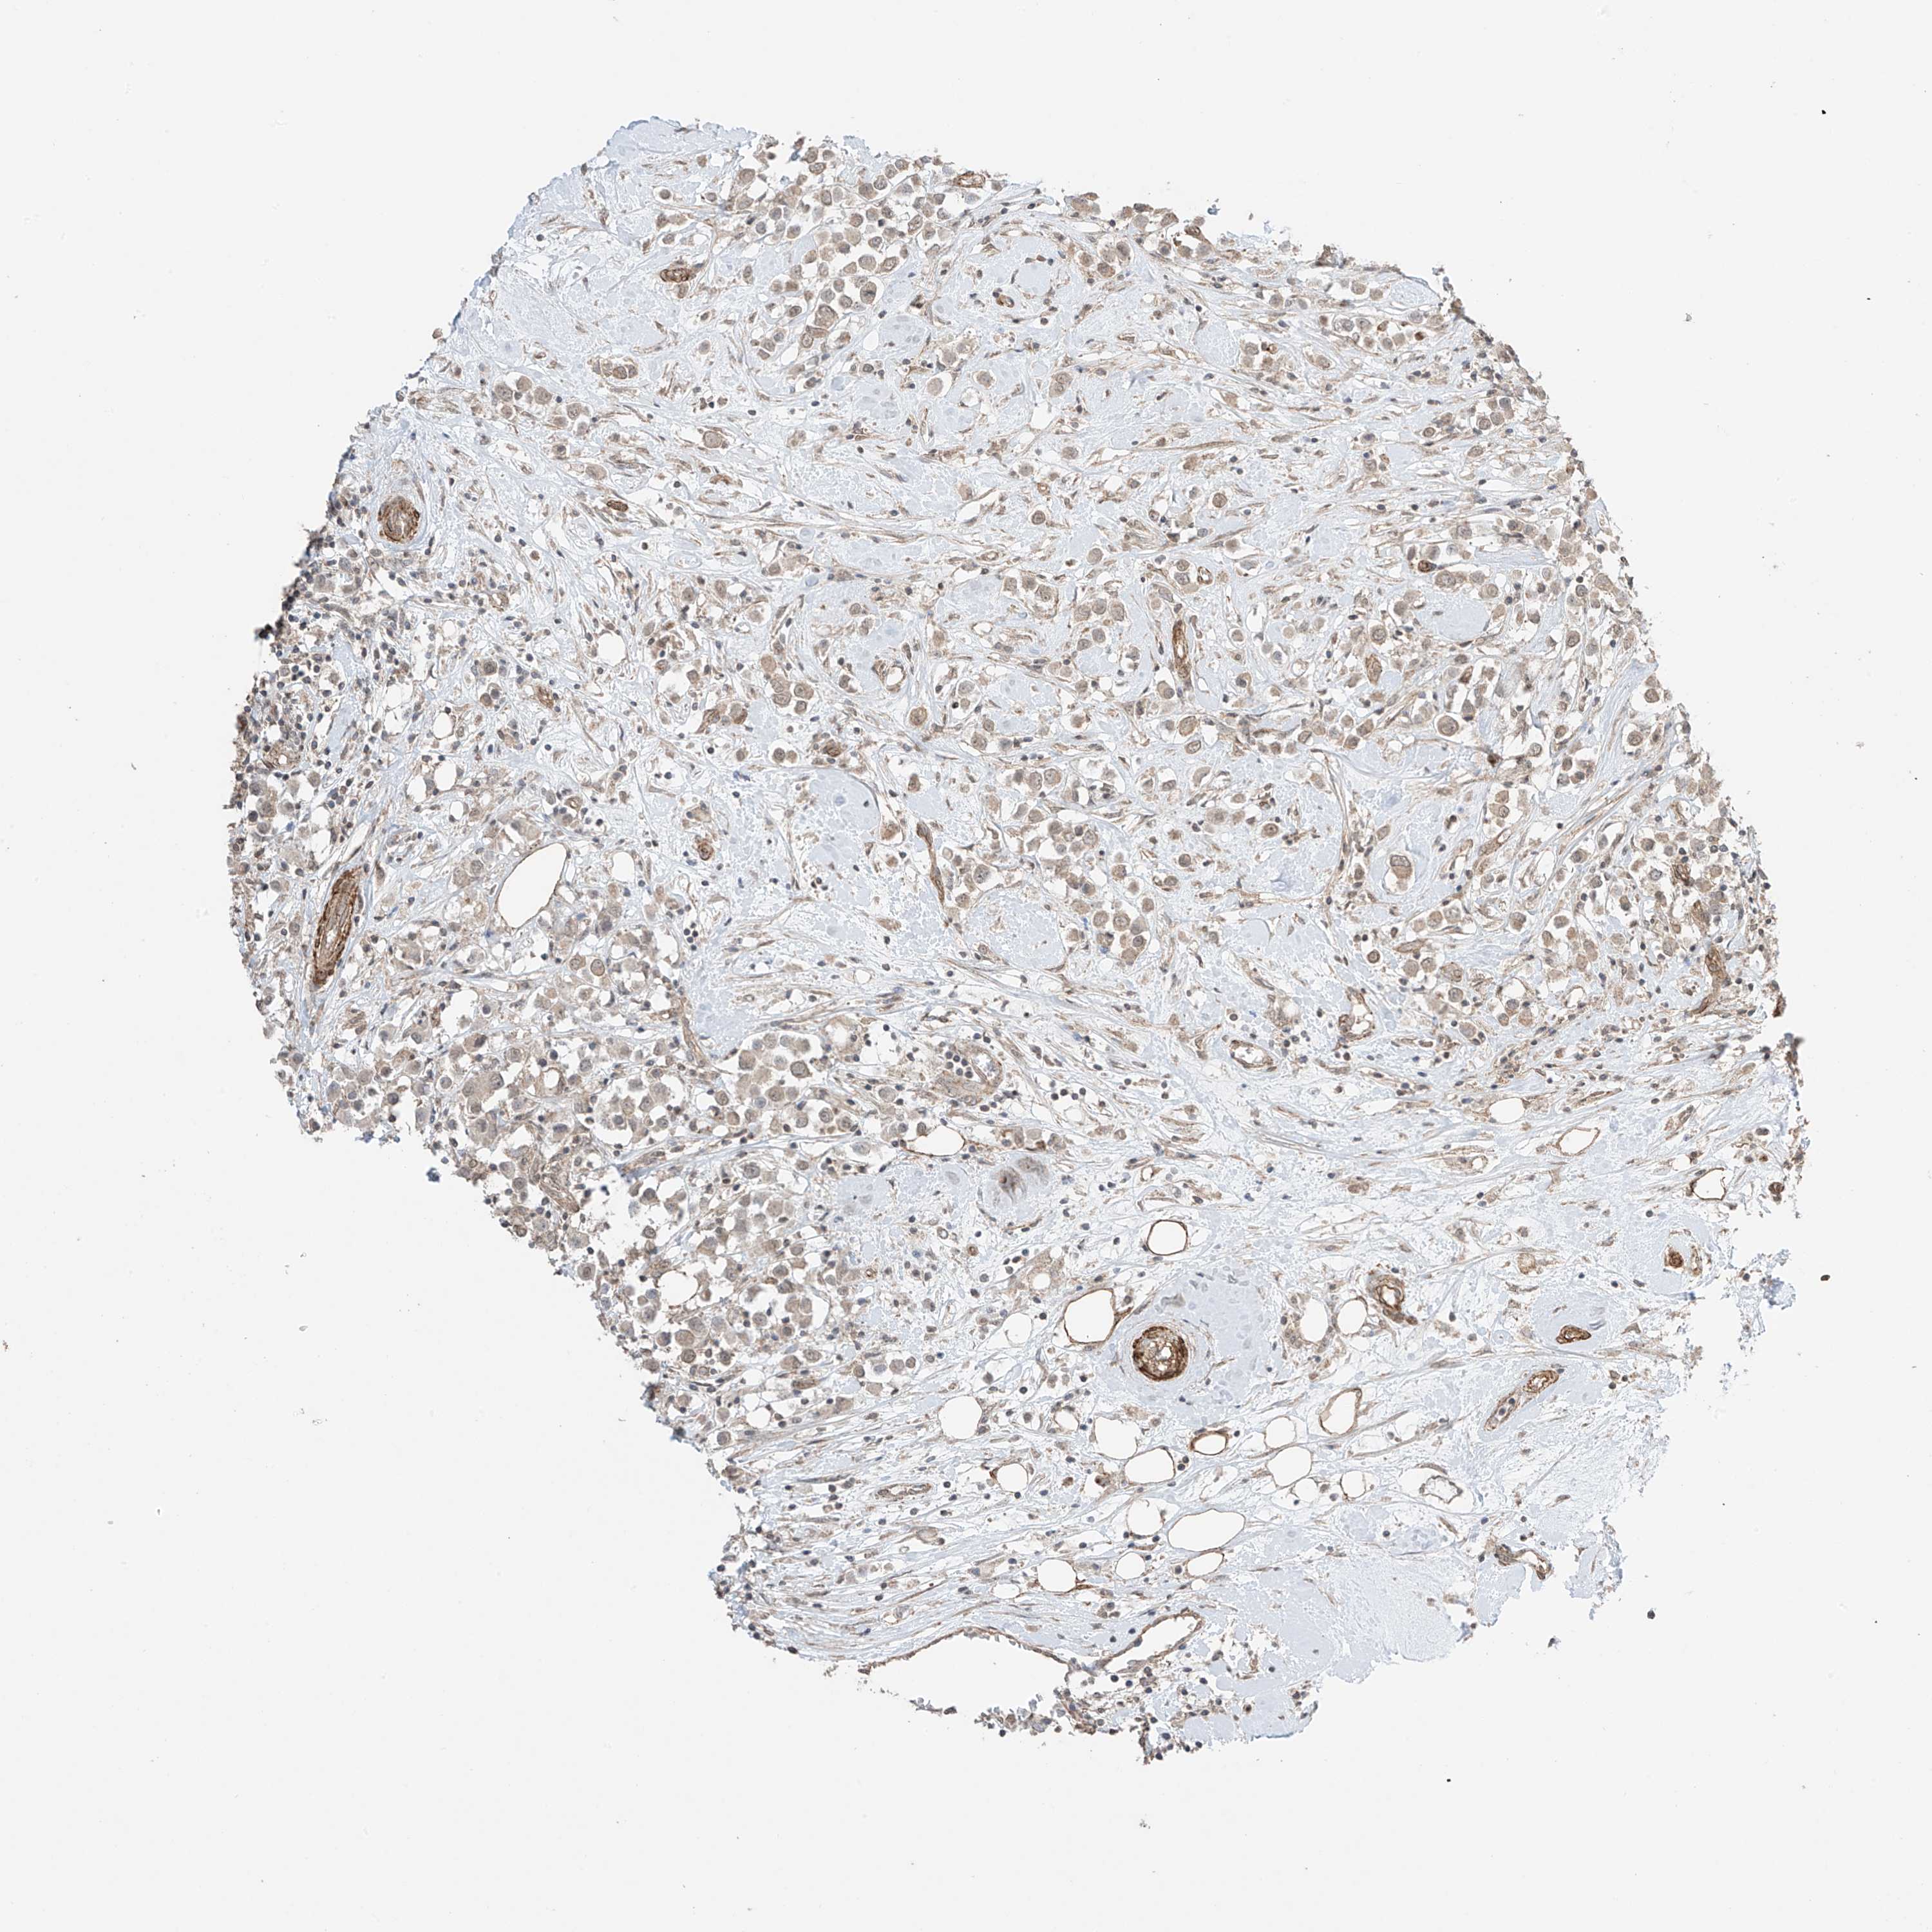

CANCER BREAST CANCER Show tissue menu

BRCA TCGA BRCA VALIDATION PROTEIN EXPRESSION